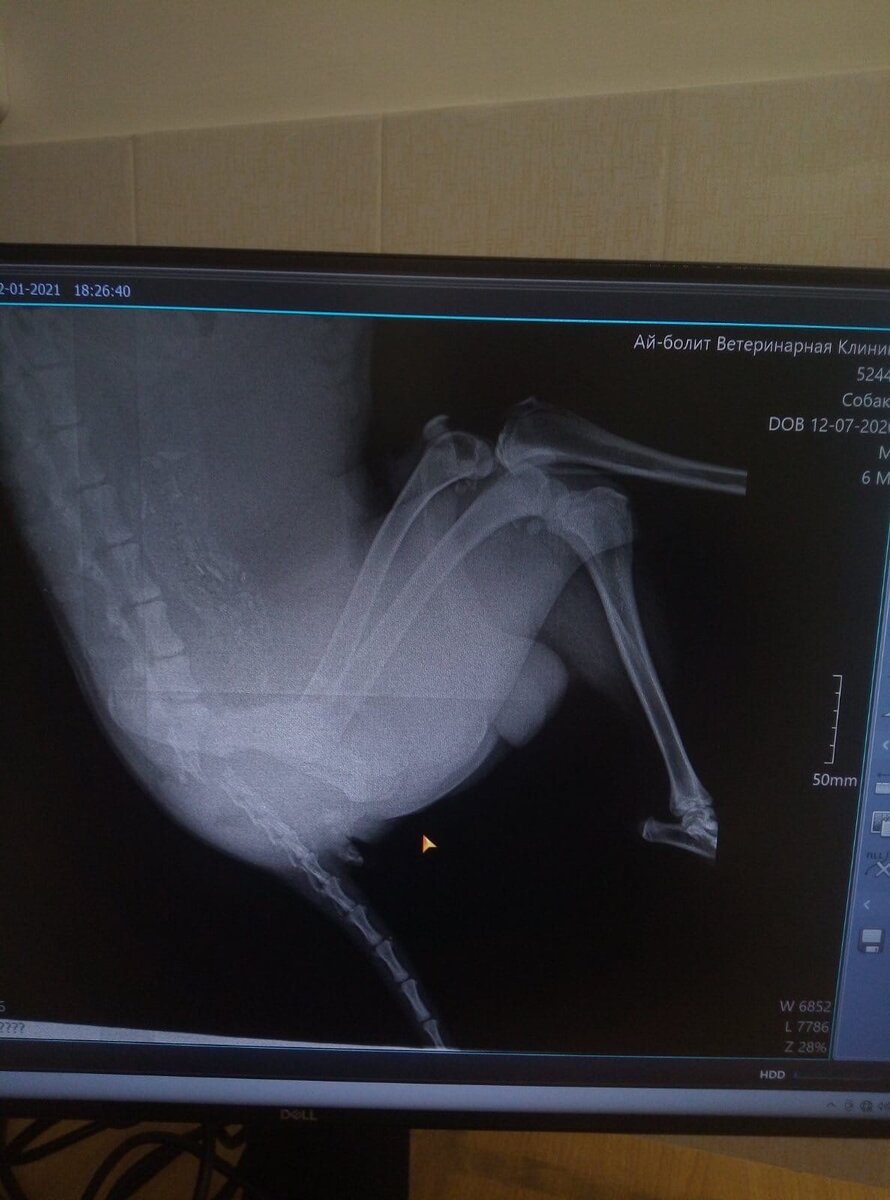

Парнишку прооперировали. Щенок был весь сломан, больше всего пострадал таз, несколько переломов. Так же отрыв хвоста.